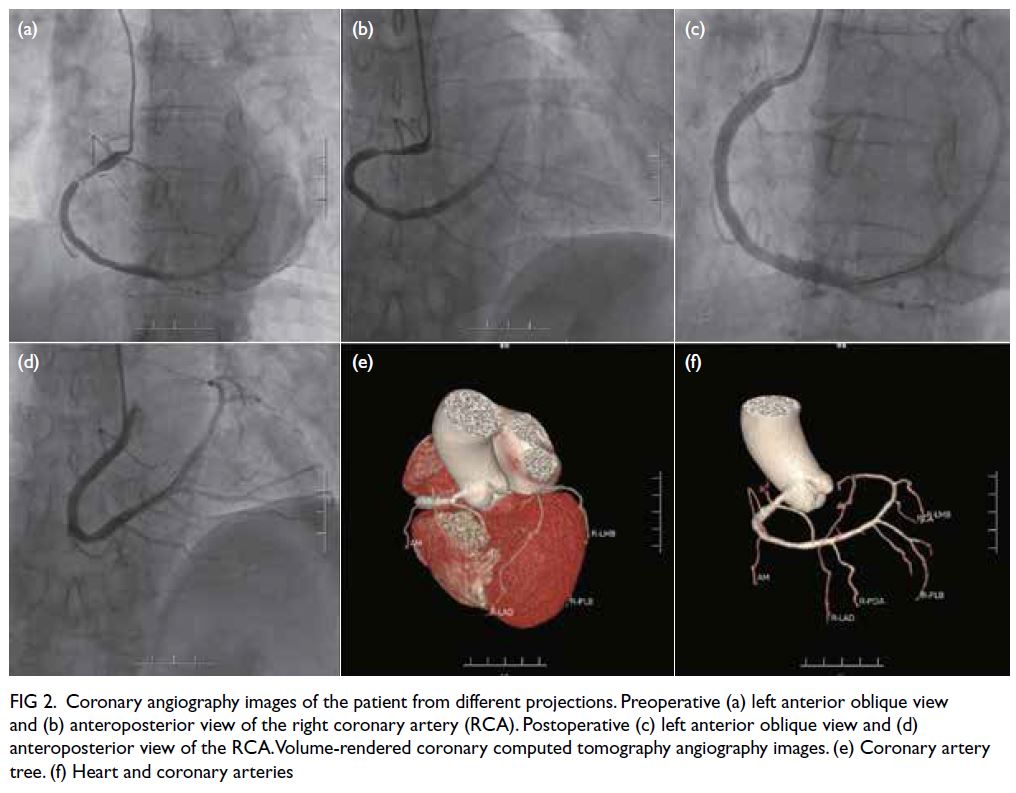

Thrombolysis in Myocardial Ischemia Trial III) [Fig 2a-d]. Postoperatively, the patient reported no pain

Figure 2. Coronary angiography images of the patient from different projections. Preoperative (a) left anterior oblique view and (b) anteroposterior view of the right coronary artery (RCA). Postoperative (c) left anterior oblique view and (d) anteroposterior view of the RCA. Volume-rendered coronary computed tomography angiography images. (e) Coronary artery tree. (f) Heart and coronary arteries

Coronary computed tomography angiography

(CTA) [Fig 2e and f] revealed that the left main trunk,

LAD, and left circumflex artery did not arise from

the left coronary sinus. The RCA originated from the

right coronary sinus. These results aligned with the